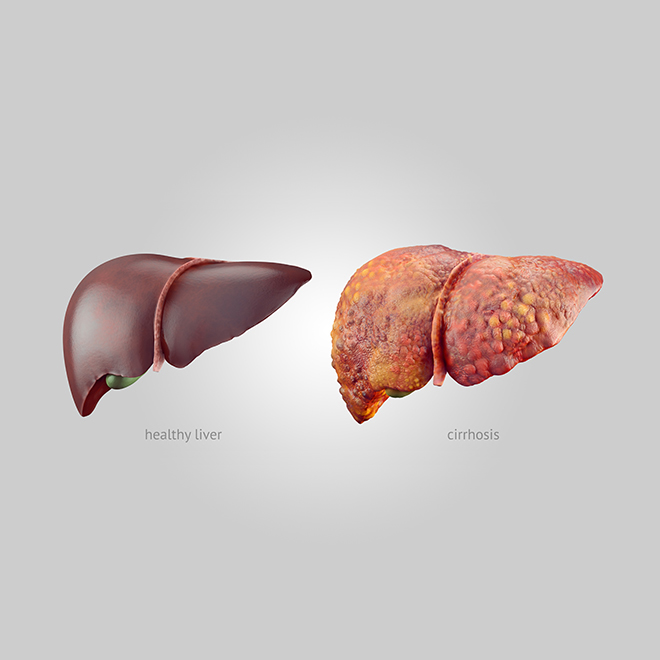

Liver Cirrhosis